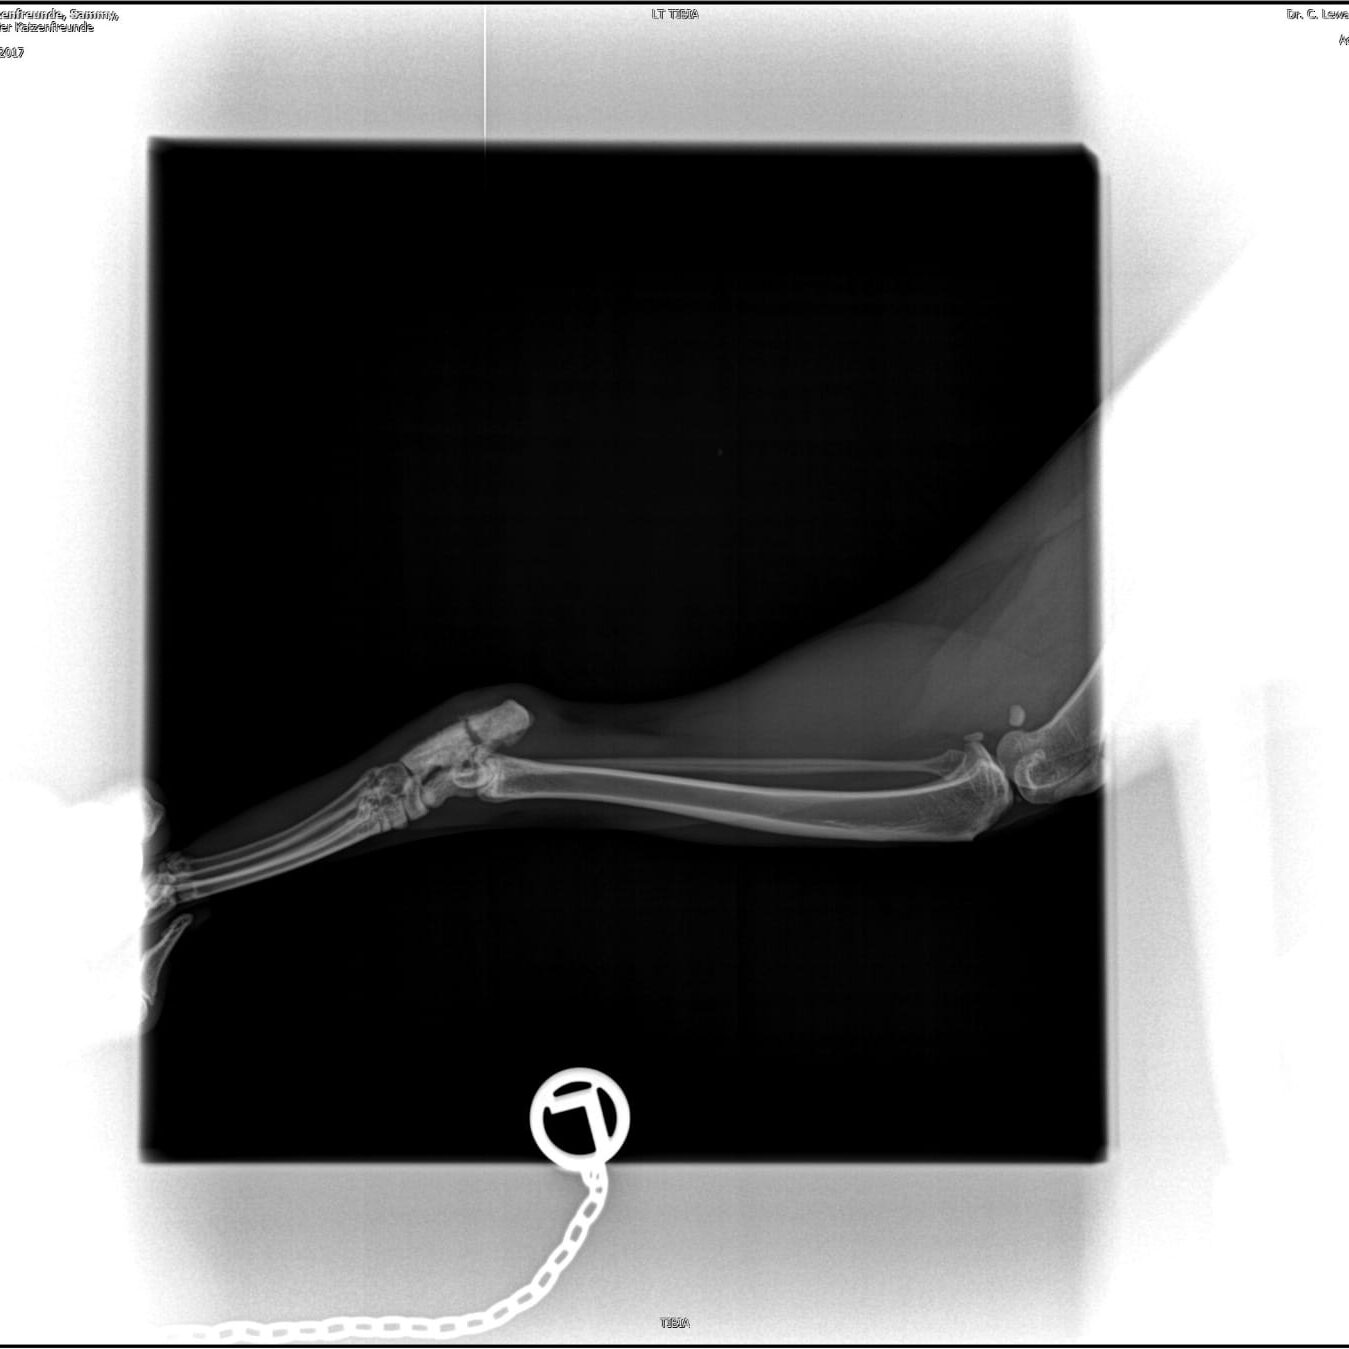

Nach Sammys zweiter OP zeigte sich, dass die Schraube der eingesetzten Platte sichtbar ist (Siehe Bild). Dadurch wurde der Heilerfolg noch schwieriger. Mittlerweile drückt sich die Schraube immer mehr heraus. Leider konnten wir nichts daran ändern. Die Wunde musste einige Wochen heilen, damit sich neues Gewebe bilden konnte, sonst hätte keine Möglichkeit bestanden, die eingesetzte Platte zu entfernen. In einer Woche entscheidet sich, was genau die nächsten Schritte sind. Sammy wird aber nochmal operiert werden müssen. Das ist jetzt seine vierte OP.